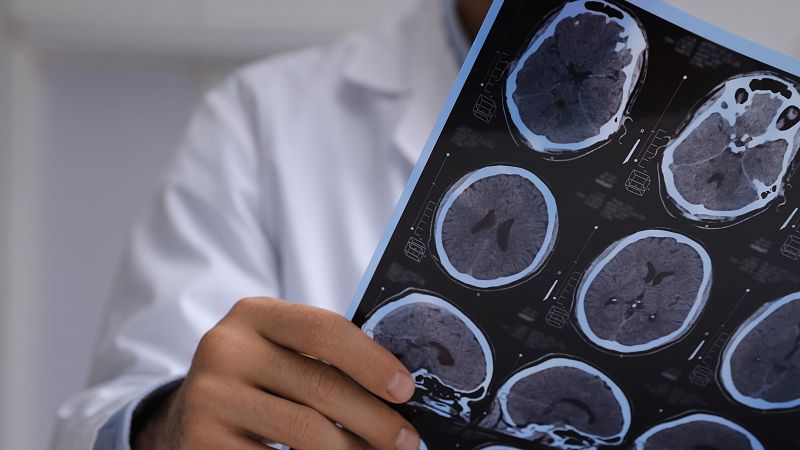

- En España hay más de 430.000 afectados por Daño Cerebral Adquirido debido a ictus o accidentes

- La media del coste bruto de un paciente de este tipo es de 10.000 euros al mes